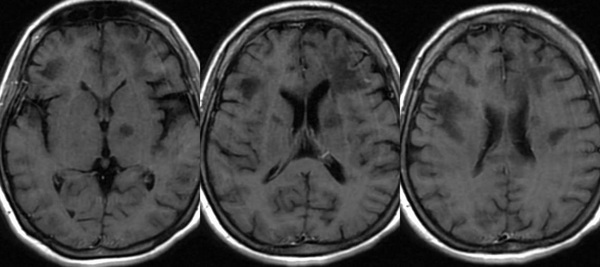

3. Bệnh chất trắng đa ổ tiến triển (PML)

Căn bệnh kỳ lạ này được miêu tả như một chứng rối loạn thần kinh. Chứng bệnh (Progressive Multifocal Leukoencephalopathy - PML) này được đặc trưng bởi sự phá hủy các tế bào sản xuất myelin.

Myelin là một chất dạng dầu có tác dụng bảo vệ hệ thần kinh trong não và tủy sống con người hay còn được gọi là chất trắng của hệ thống thần kinh trung ương.

Bằng cách này, căn bệnh phá hủy dần lớp màng bảo vệ các dây thần kinh trong não bộ. Nó gây ra sự suy giảm hoạt động não, biểu hiện là chân tay yếu khó cử động, mất trí nhớ, mất ngôn ngữ... và có thể dẫn đến cái chết. Căn bệnh này bị gây ra bởi một loại virus có tên JC.

Tuy nhiên virus JC chỉ gây bệnh khi hệ miễn dịch bị suy yếu nghiêm trọng chẳng hạn như ở người nhiễm HIV/AIDS, có khối u ác tính huyết học hay ở người được ghép nội tạng buộc phải sử dụng thuốc ức chế miễn dịch. Nhìn chung tỉ lệ mắc bệnh PML là khoảng 1/200.000 người.

PML phá hủy dần não bộ.

Căn bệnh này vẫn là đề tài nghiên cứu đau đầu của các nhà khoa học bởi hiện nay, các chuyên gia vẫn chưa có biện pháp nào để phòng ngừa hay tiêu diệt loại virus này, tránh không cho nó phát bệnh.